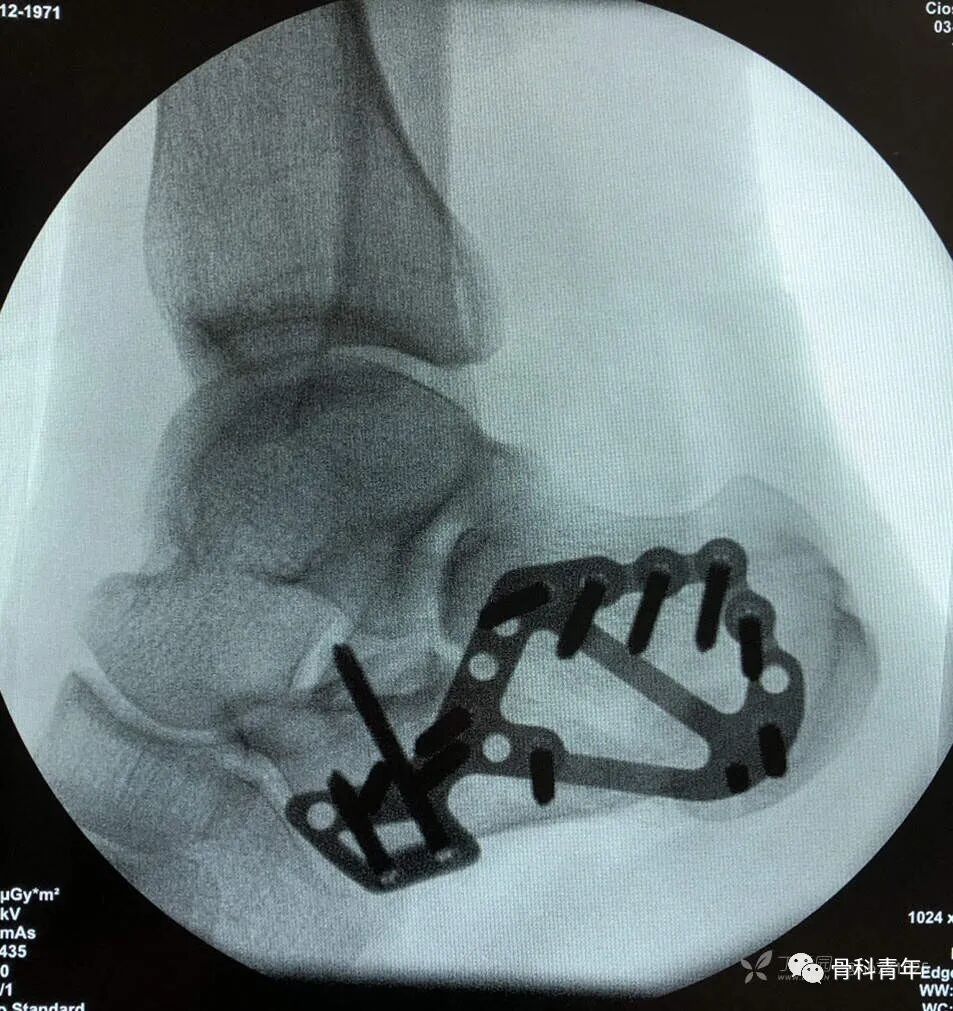

14.跟骨骨折(跗骨窦入路)

15.跟骨骨折(L入路)